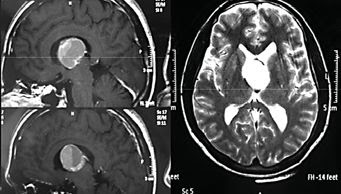

Hematoma intraventricular encapsulado: un caso

Chronic Intraventricular Encapsulated Hematoma in an Adult: A Case Report

E. Kechagiasa C. Ioakimidoub N. Georgakouliasa

A. Seretisa G. Kontogeorgosb

Departments of aNeurosurgery and bPathology, General Hospital of Athens

‘G. Gennimatas’, Athens, Greece

mail del autor: vagelis_kechagias @ yahoo.gr